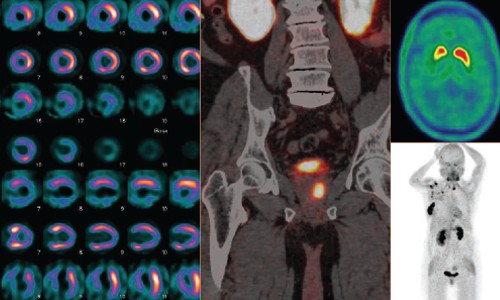

PET /CT

PET/CT is a powerful imaging technique that helps in the diagnosis and treatment of many diseases especially Cancers, Alzheimer’s disease, Infections, etc. It can detect diseases that are not identified on conventional CT scans. PET/CT scan consists of 2 components - the diagnostic CT (Computerized Tomography) scan (anatomical) and the PET (Positron Emission Tomography) scan (functional) - both in the same sitting. Therefore PET/CT accurately images metabolic and anatomic information in the body.

The GE IQ PET/CT at MIOT International (1st of its kind in South India) offers Superior Image Quality and Intelligent Quantitation which enables the Physician to discover and diagnose cancer confidently. Now, we can detect even minute abnormalities and offer accurate diagnosis and monitoring for our patients.